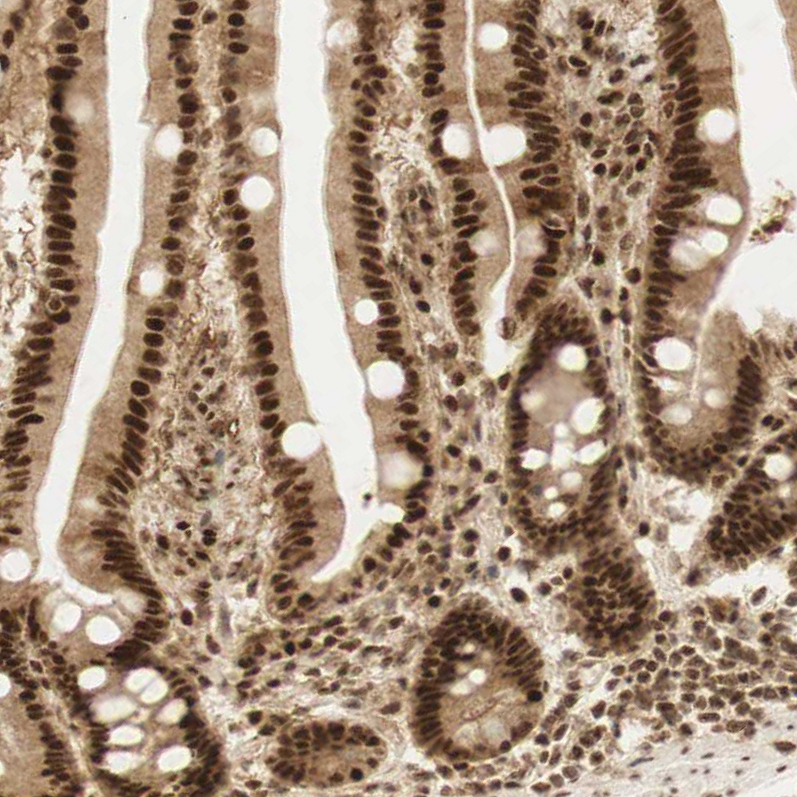

Immunohistochemical staining of human bone marrow shows strong nuclear positivity in hematopoietic cells.